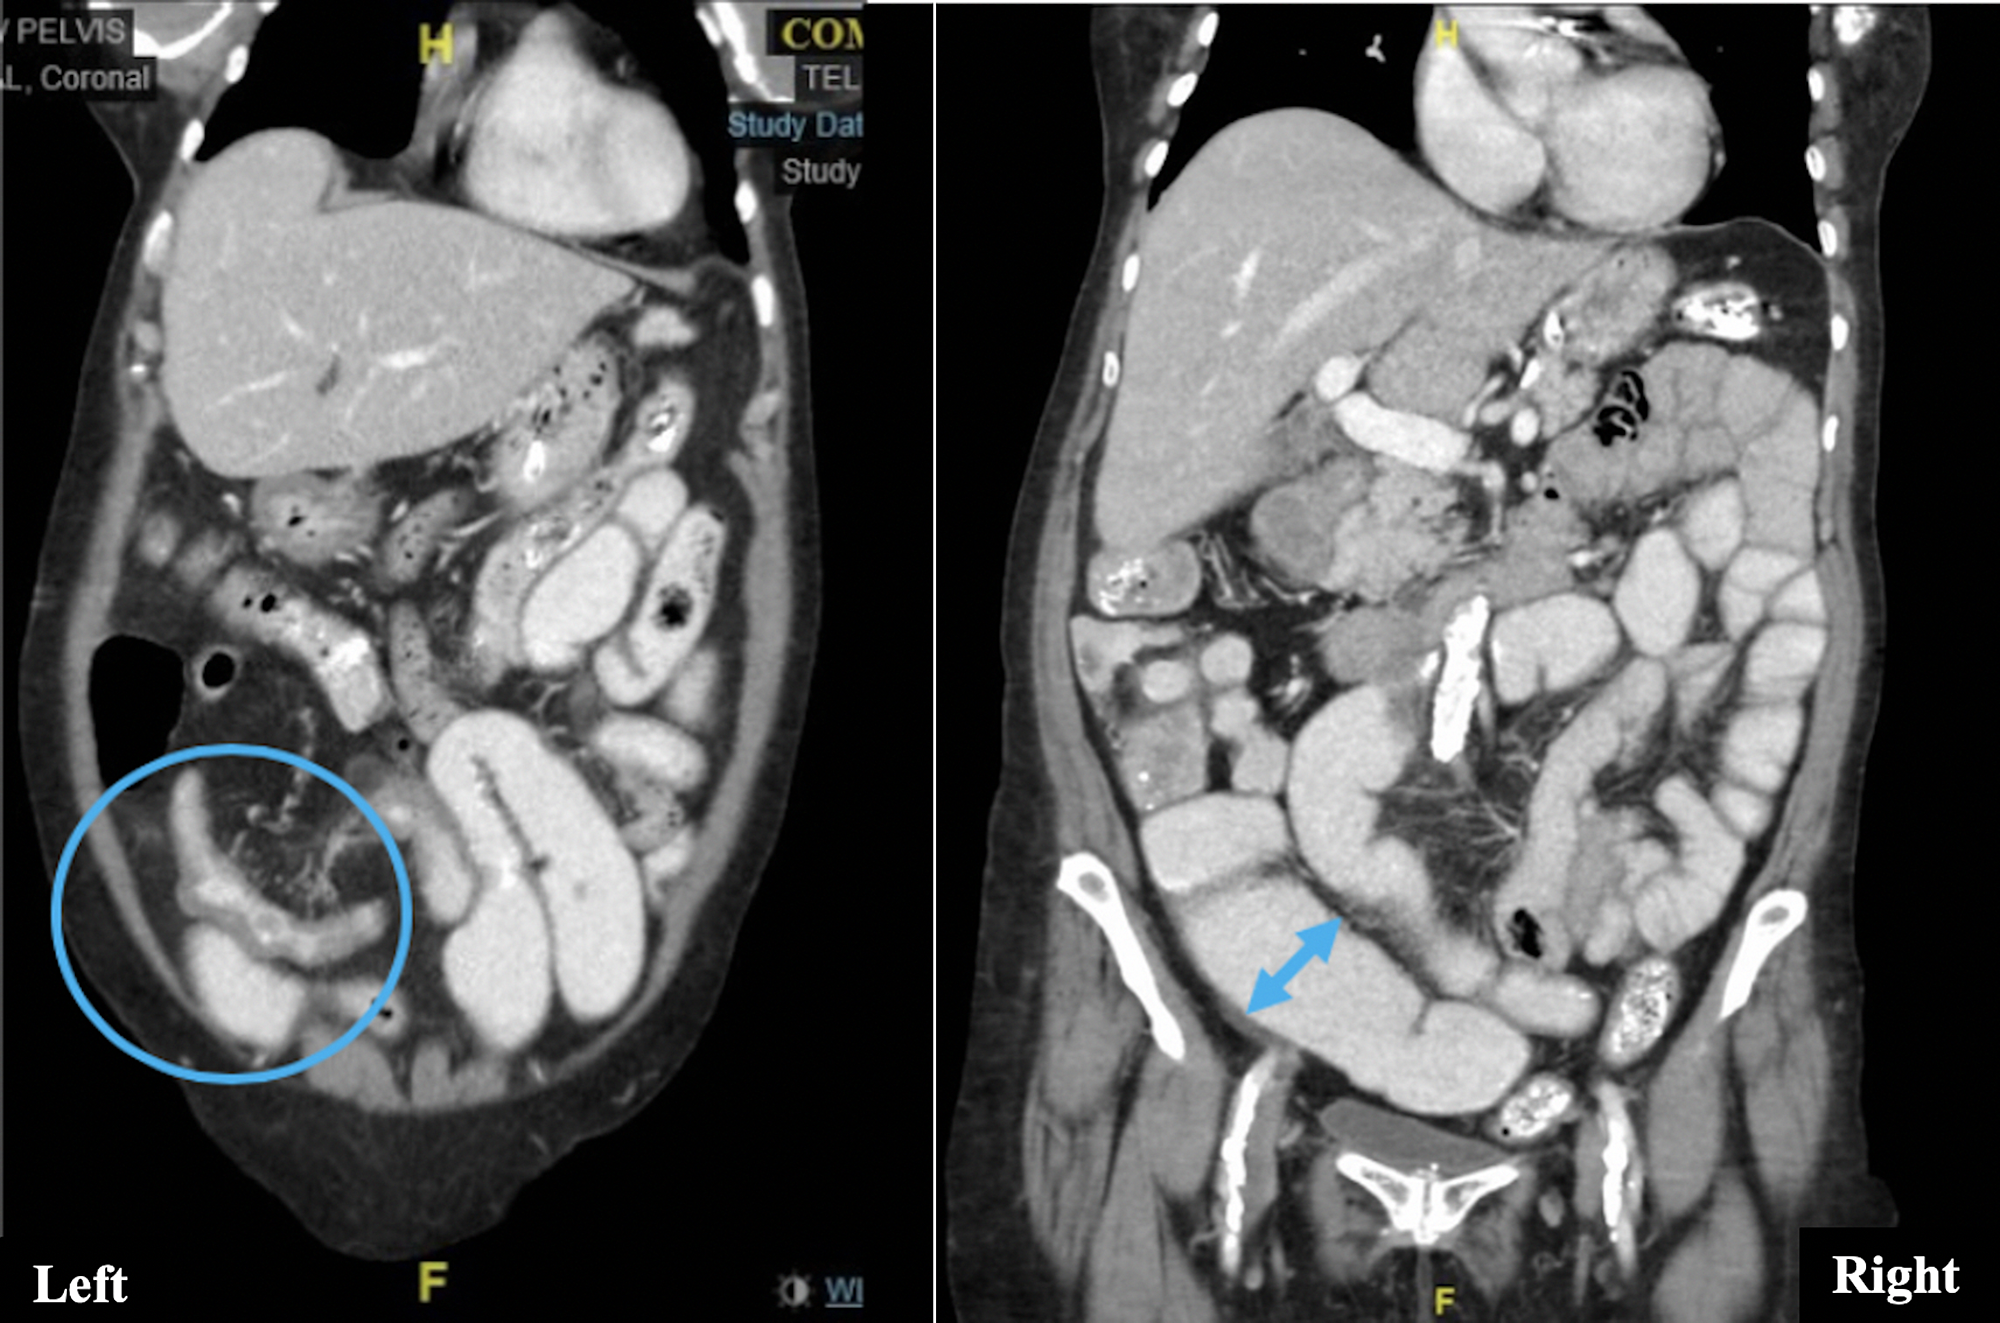

Contrast fluoroscopy and CT findings in TB and Crohn's disease Crohn's And Tb the differential diagnosis between intestinal tuberculosis and crohn's disease has always been an important concern in asia. differentiating crohn’s disease (cd) from intestinal tuberculosis (itb) is a diagnostic dilemma, particularly in regions. differentiation between crohn’s disease and intestinal tuberculosis is difficult but crucial for medical decisions. discriminating intestinal tuberculosis (itb) and crohn disease (cd) remains an. Crohn's And Tb.